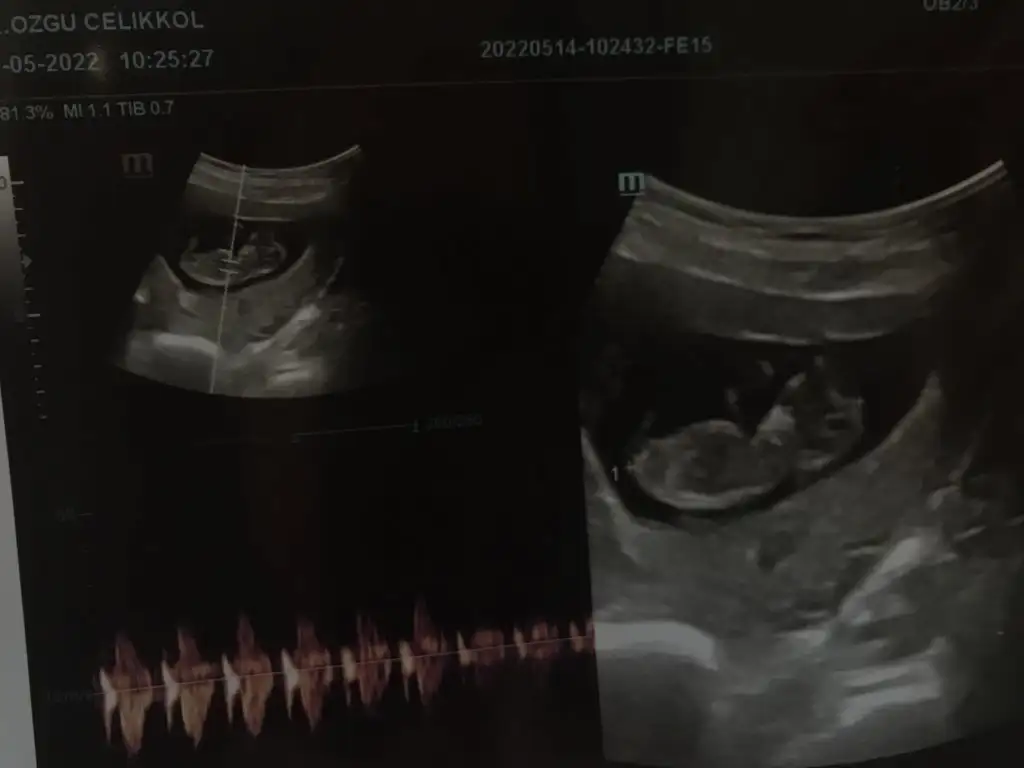

paşacık geliyorCinsiyet tahmin eder misiniz bu konuda tecrübeli bilen arkadaşlar yardımınızı rica ediyorım 10+6 yız bu resimlerde

Tahmin dogru cikti doktorum 13. Haftada erkek dedi. Tesekkur ederimmmpaşa gibi

bir annemize yapılan yorum daha tuttuTahmin dogru cikti doktorum 13. Haftada erkek dedi. Tesekkur ederimmm

birinde bebek henüz yok diğerinde ise yolk sac çok büyük tahmin yapılamazmerhabalar 7 haftalık vajınadan ikiz bebek

paşa gibi7+1 karından usg canım